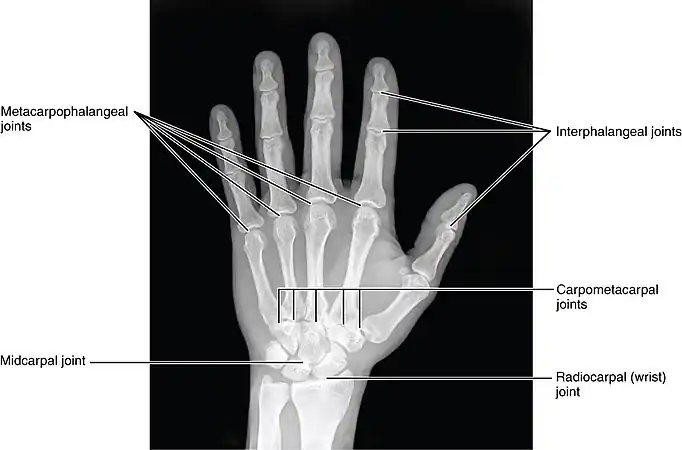

The DIP, PIP and MCP joints of the hand:

The interphalangeal joints of the hand are the hinge joints between the phalanges of the fingers that provide flexion towards the palm of the hand.

There are two sets in each finger (except in the thumb, which has only one joint):

- "proximal interphalangeal joints" (PIJ or PIP), those between the first (also called proximal) and second (intermediate) phalanges

- "distal interphalangeal joints" (DIJ or DIP), those between the second (intermediate) and third (distal) phalanges

Joint structure

The PIP joint exhibits great lateral stability. Its transverse diameter is greater than its antero-posterior diameter and its thick collateral ligaments are tight in all positions during flexion, contrary to those in the metacarpophalangeal joint.[1]